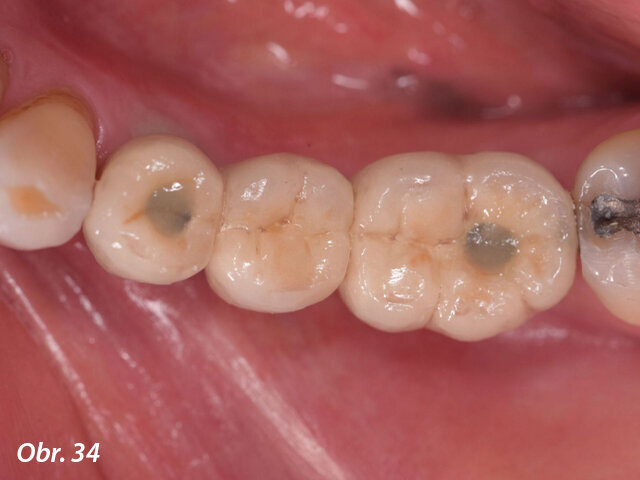

Klinické vyšetření třetího kvadrantu zjistilo zuby s recesy gingivy, mobilitou i ztrátou zubní hmoty. Pacient pociťoval bolest a nepohodu v oblasti fixního můstku v oblasti zubu 34 až 36. Ve frontálním úseku třetího kvadrantu bylo patrné omezené množství keratinizovaných tkání. Orální hygiena byla vyhodnocena jako vyhovující.

Léčba zahrnovala dentální profylaxi, udělení pokynů k orální hygieně a extrakci zbytků zubu 38 a z klinického hlediska beznadějných zubů 34 a 36.